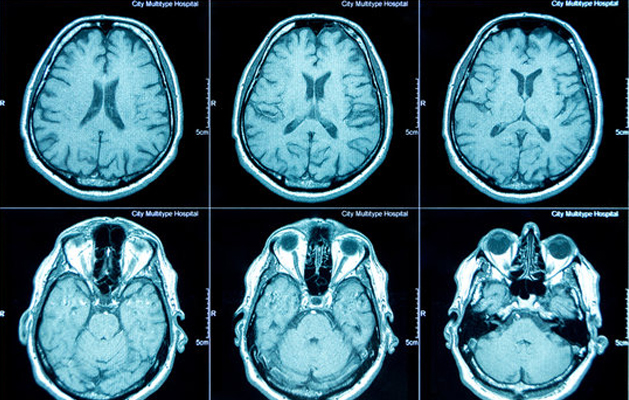

Best Clinical CT SCAN 24 Hours in Chennai

Computed Tomography (CT) scan is a powerful X-ray procedure that produces detailed pictures, or slices, of the body. It is also called computerized tomography and computed axial tomography (CAT). A CT scan shows detailed images of any part of the body, including the bones, muscles, fat, and organs. CT scans are more detailed than conventional X-rays. A special machine linked to a computer makes the CT images. The images can then be examined on a computer screen or printed. CT scans are painless and noninvasive. No anesthesia is needed. The radiation exposure from a CT scan is low compared with other diagnostic tests such as conventional X-rays. During a CT scan, you lie on a narrow table that slides through the center of the machine. You may be asked to hold your breath for short periods of time to avoid blurring the images. The test takes about 30 minutes. The information from a CT scan can be used to diagnose problems such as infections, tumors, bleeding in the brain, or injuries to the spine or organs. It can also help guide procedures such as surgery or biopsies (removal of tissue samples).

A CT scan is usually prescribed when there is a need for more detailed information than what can be obtained from an X-ray or physical examination. This may include conditions such as tumors, internal bleeding, and broken bones. CT scan can also be used to guide physicians and surgeons during biopsies, fluid drainage, and other treatments. In addition, CT scans are often prescribed by doctors to detect and diagnose diseases such as cancer, stroke, and heart disease.

A CT scan is a medical procedure that uses x-rays and computer technology to create detailed images of the inside of your body. CT stands for computed tomography. During a CT scan, you lie on a table and an x-ray machine circles around you, taking pictures of cross-sections of your body. The pictures are sent to a computer, where they are converted into 3-D images. Your doctor can use these images to diagnose problems or plan treatments. CT scans are painless and take about 30 minutes. You may be given a contrast material or get an intravenous (IV) line before the CT scan starts. The contrast material helps the radiologist see certain areas more clearly. If you have an IV line, the contrast material will be injected through it during the CT scan. After the CT scan is complete, you can go home and resume your normal activities. You should not have any side effects from the contrast material used during a CT scan. However, if you have an allergy to iodine, tell your doctor before having a CT scan so that he or she can prescribe medicine to lessen the chance of an allergic reaction. Very few might feel some discomfort from lying on the table during the procedure. You may also hear buzzing and clicking noises as the x-ray machine moves around you during the CT scan. Most people find these noises faint and do not find them bothersome. Some people may feel anxious or claustrophobic while lying still inside the small space of a CT scanner for long periods of time.